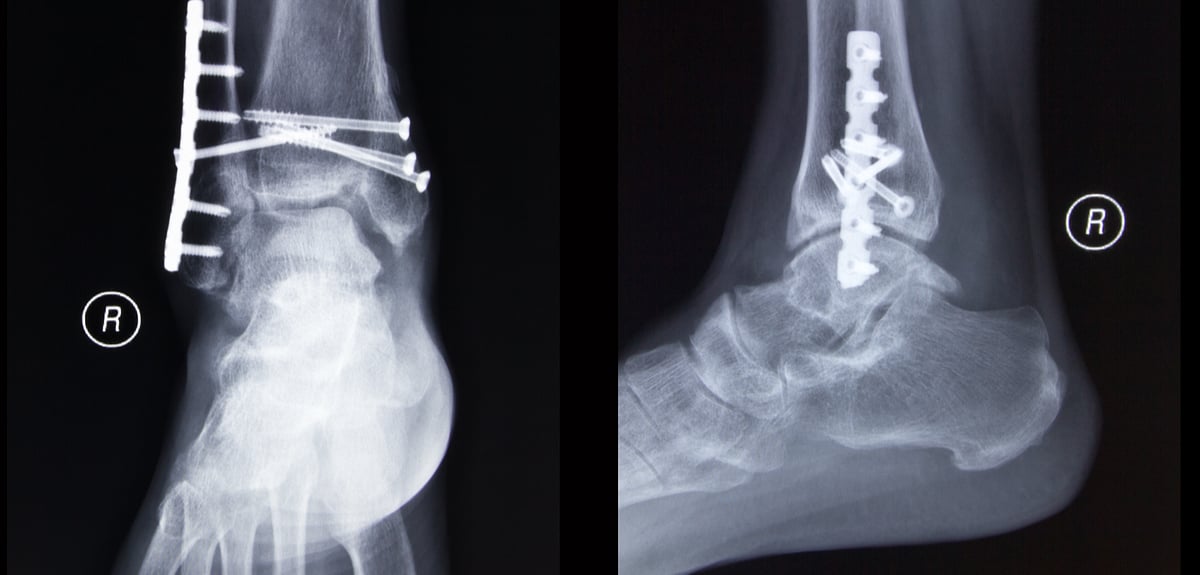

Every procedure performed at the orthopaedic surgery center has been assigned one all‐inclusive charge, which includes the facility fee, the surgeon’s fee, and the anesthesiologist’s fee. For example, surgery for a fractured ankle costs between $9,719 and $17,634, not including the doctor fee, according to a cost calculator from saint elizabeth regional medical center [ 4] in lincoln, nebraska. Foot and ankle surgery abroad costs foot and ankle surgery is performed by orthopaedic surgeons, many of whom also have a specialism in the treatment of lower limb conditions.

How much does an ankle ligament repair or reconstruction cost? Common procedures performed by foot and ankle surgeons include ankle replacement, ankle fusion, bunion surgery and repair of the achilles tendon. The procedure is fairly simple to perform and would cost in the ballpark number of around $4,000.

Learn about costs, procedure and recovery. For example, a major joint replacement for a lower extremity would cost about $29,643 not including the surgeon fee, according to baptist memorial health care in memphis, tennessee. Baltimore, md foot or ankle fusion surgery cost average: